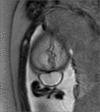

Case description: We present a case of a female patient in utero of 26 gestational weeks with the diagnosis of an occipital encephalocele treated by open fetal surgery. During week 20 of gestation, the diagnosis of occipital encephalocele was made by ultrasound, which was corroborated by fetal magnetic resonance that showed cranial protrusion of neural and meningeal content in the occipital region, measuring 1.6 × 2.8 × 3.3 cm with an approximate volume of 7.7 cc through a bone defect of 6 mm. The closure of the defect was performed by the postnatal surgical technique adapted to the open fetal surgery. Later, the patient was born transabdominal with a 2.8 cm occipital wound, with suture points and approximated borders, normocephalic, without clinical signs of sepsis, hydrocephalus, or overt neurologic compromise.